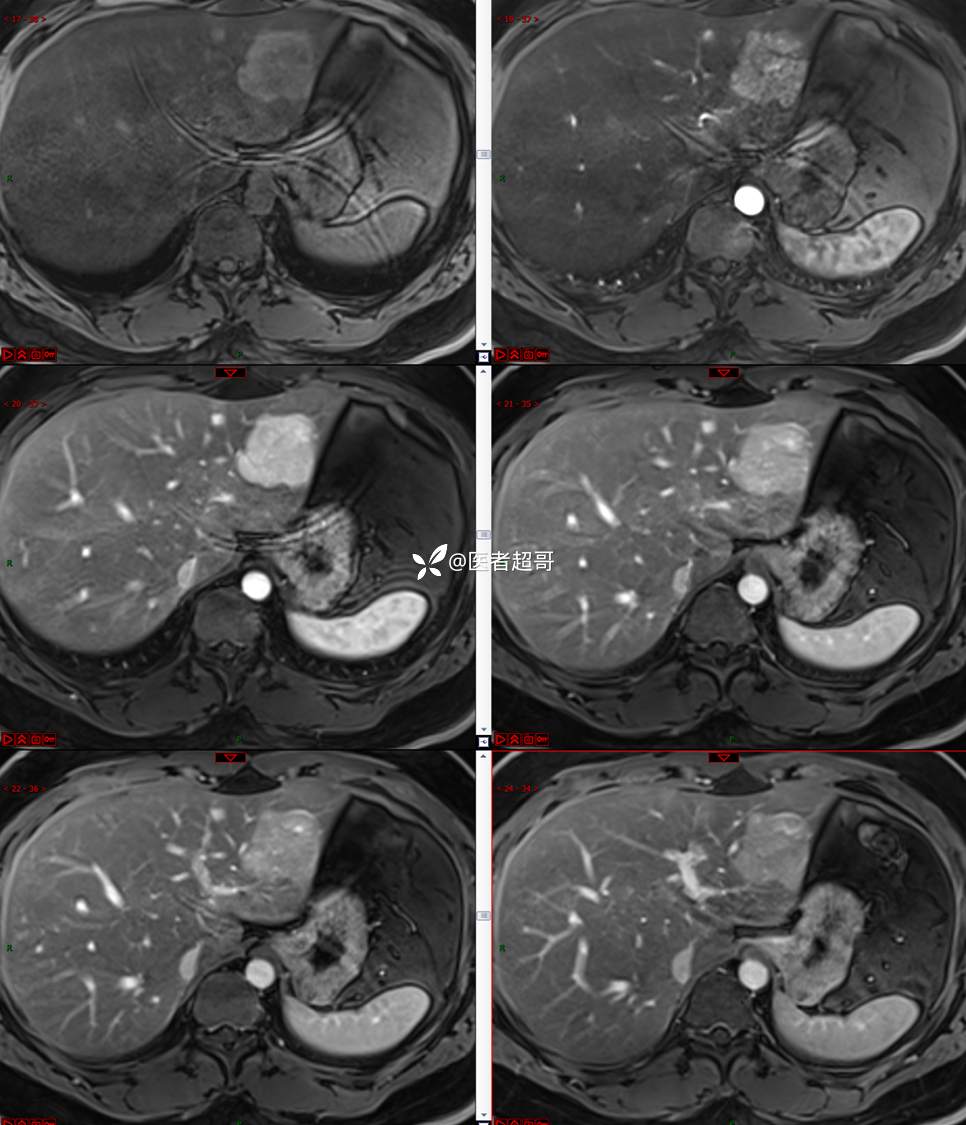

【影诊笔记685】男,31y,发现肝占位性病变5天就诊,请诊断分析,有病理结果!

主 诉:发现肝占位性病变5天。

现病史:患者缘于5天前体检时发现肝占位性病变,未予以特殊处置。现患者为求系统诊治就诊于我院,行普美显提示:肝左叶富血供占位,请结合临床及其他检查,肝多发血管瘤,脂肪肝,肝囊肿,请结合临床。门诊以“肝占位性病变”收入我科。病程中,饮食睡眠可,二便可,近期体重未见明显变化。